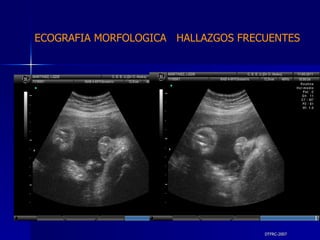

DTFRC-2007 ECOGRAFIA MORFOLOGICA  HALLAZGOS FRECUENTES   MATERIAL Y METODO ES UN ESTUDIO DESCRIPTIVO, RETROSPECTIVO  DE ESTUDIO ECOGRA FICOS REALIZADOS ENTRE MARZO 07 A MARZO 08 EQUIPO DE ALTA RESOLUCION   VOLUSON 730 PRO  MEDISON SA 8000 live MEDISON SA 8000SE CRITERIO DE INCLUSION:   POBLACION GENERAL    GESTACIONES  20 a 24 SEMANAS   UNIVERSO  N 211

DTFRC-2007 ECOGRAFIA MORFOLOGICA  HALLAZGOS FRECUENTES   Sistema Nervioso Central  8  Cardiovascular  0 Genitourinario  6 Musculos Esqueleticos  2 Gastrointestinales  2  Otros  12  Total  30   NUMEROS DE ANOMALIAS POR SISTEMA n N  211

DTFRC-2007 ECOGRAFIA MORFOLOGICA  HALLAZGOS FRECUENTES   SISTEMA NERVIOSO CENTRAL TOTAL  8  26 % 1 HIDROCEFALIA 2 VENTRICULO MEGALIA 4 QUISTE DE PLEXO COROIDEO 1 ANENCEFALIA

DTFRC-2007 ECOGRAFIA MORFOLOGICA  HALLAZGOS FRECUENTES   GENITOURINARIA DISPLASIA RENAL MULTIQUISTICA  3 HIDRONEFROSIS  2 QUISTE DE OVARIO FETAL  1 SISTEMA DIGESTIVO DILATACION INTESTINAL  2  SISTEMA ESQUELETICO   PIE BOT  2  20 % 6 % 6 %